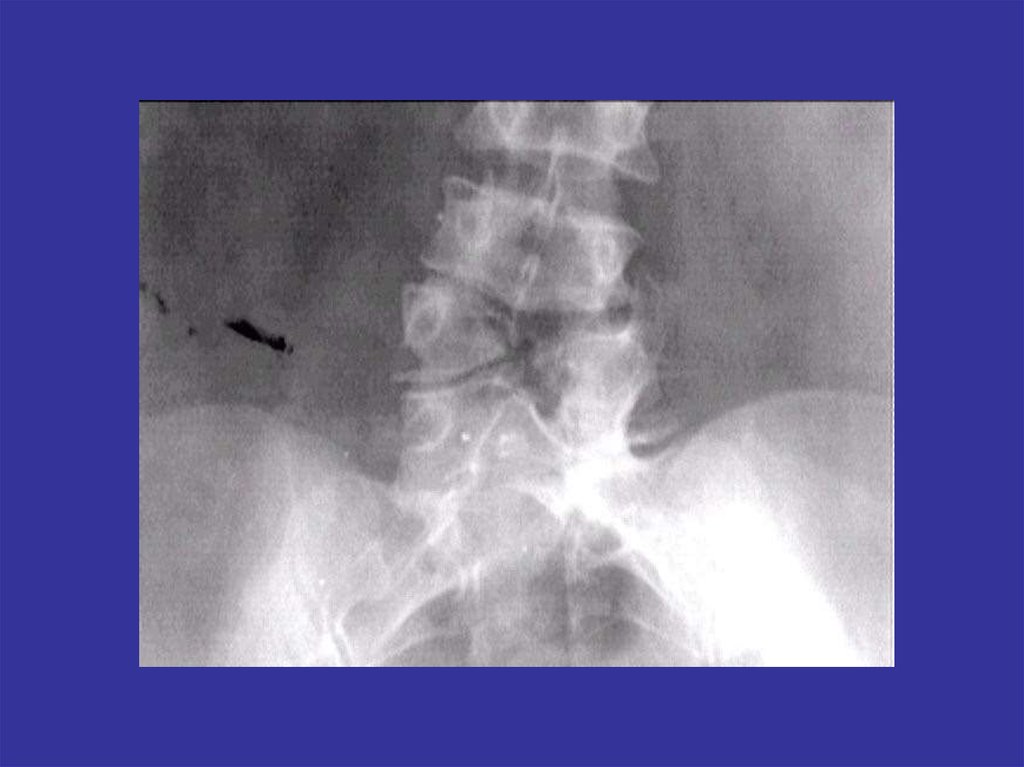

Аномалии развития позвоночника